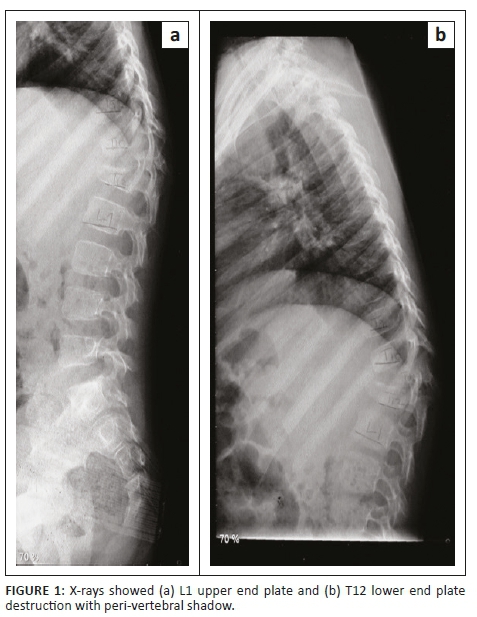

X-rays revealed kyphosis at the bottom of the thoracic spine (T12 vertebra) and the first vertebra of the lumbar spine (L1 vertebra). His T12 had vertebral destruction with preserved posterior elements. The L1 upper end plate and T12 lower end plate destruction with a peri-vertebral shadow were indicative of an abscess (Figure 1).